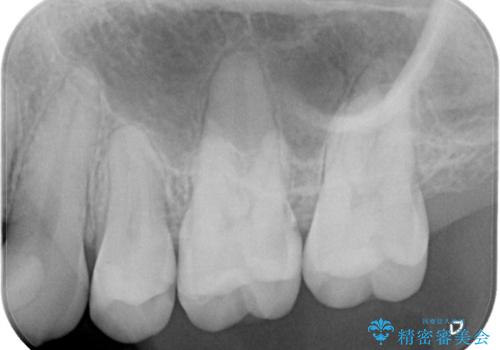

- 左上6番の奥歯のコンタクト下カリエス(歯と歯の間の虫歯)を主訴にご来院されました。レントゲンと精密診査の結果、歯と歯の間という、再発しやすい部位の虫歯であることが判明。患者様のご希望と口腔内の状態を考慮し、虫歯を徹底的に除去し、精密で再発リスクの低いセラミッククラウンで修復する治療計画を立案しました。これにより、見た目の美しさだけでなく、長期的な歯の健康維持を目指します。